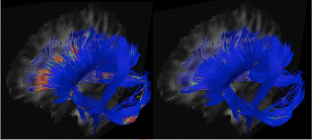

Fig. 2